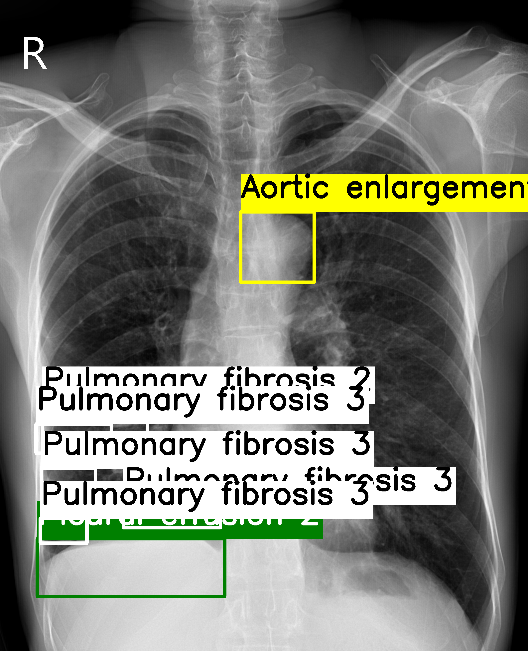

VinDR-CXR

Comparison of aggregated labels on the VinDR-CXR chest radiograph dataset. For WBF-EARL, the number beside the class label is the annotators' level of agreement while for Crowd R-CNN and BDC, the number indicates the class probability.

WBF-EARL